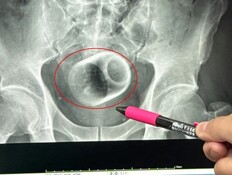

"הוצאנו מגופו צינור מתכת באורך 25 סנטימטרים"

נפל לבור כשהוא שיכור - וניצל בנס